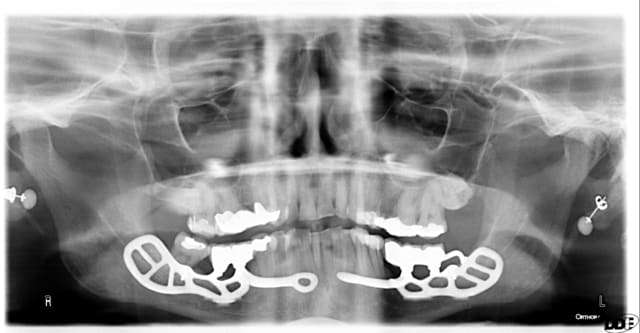

quel est la viabilité moyenne d'un implant sous-périosté?

Sous p riost  fnz2u3 - Eugenol